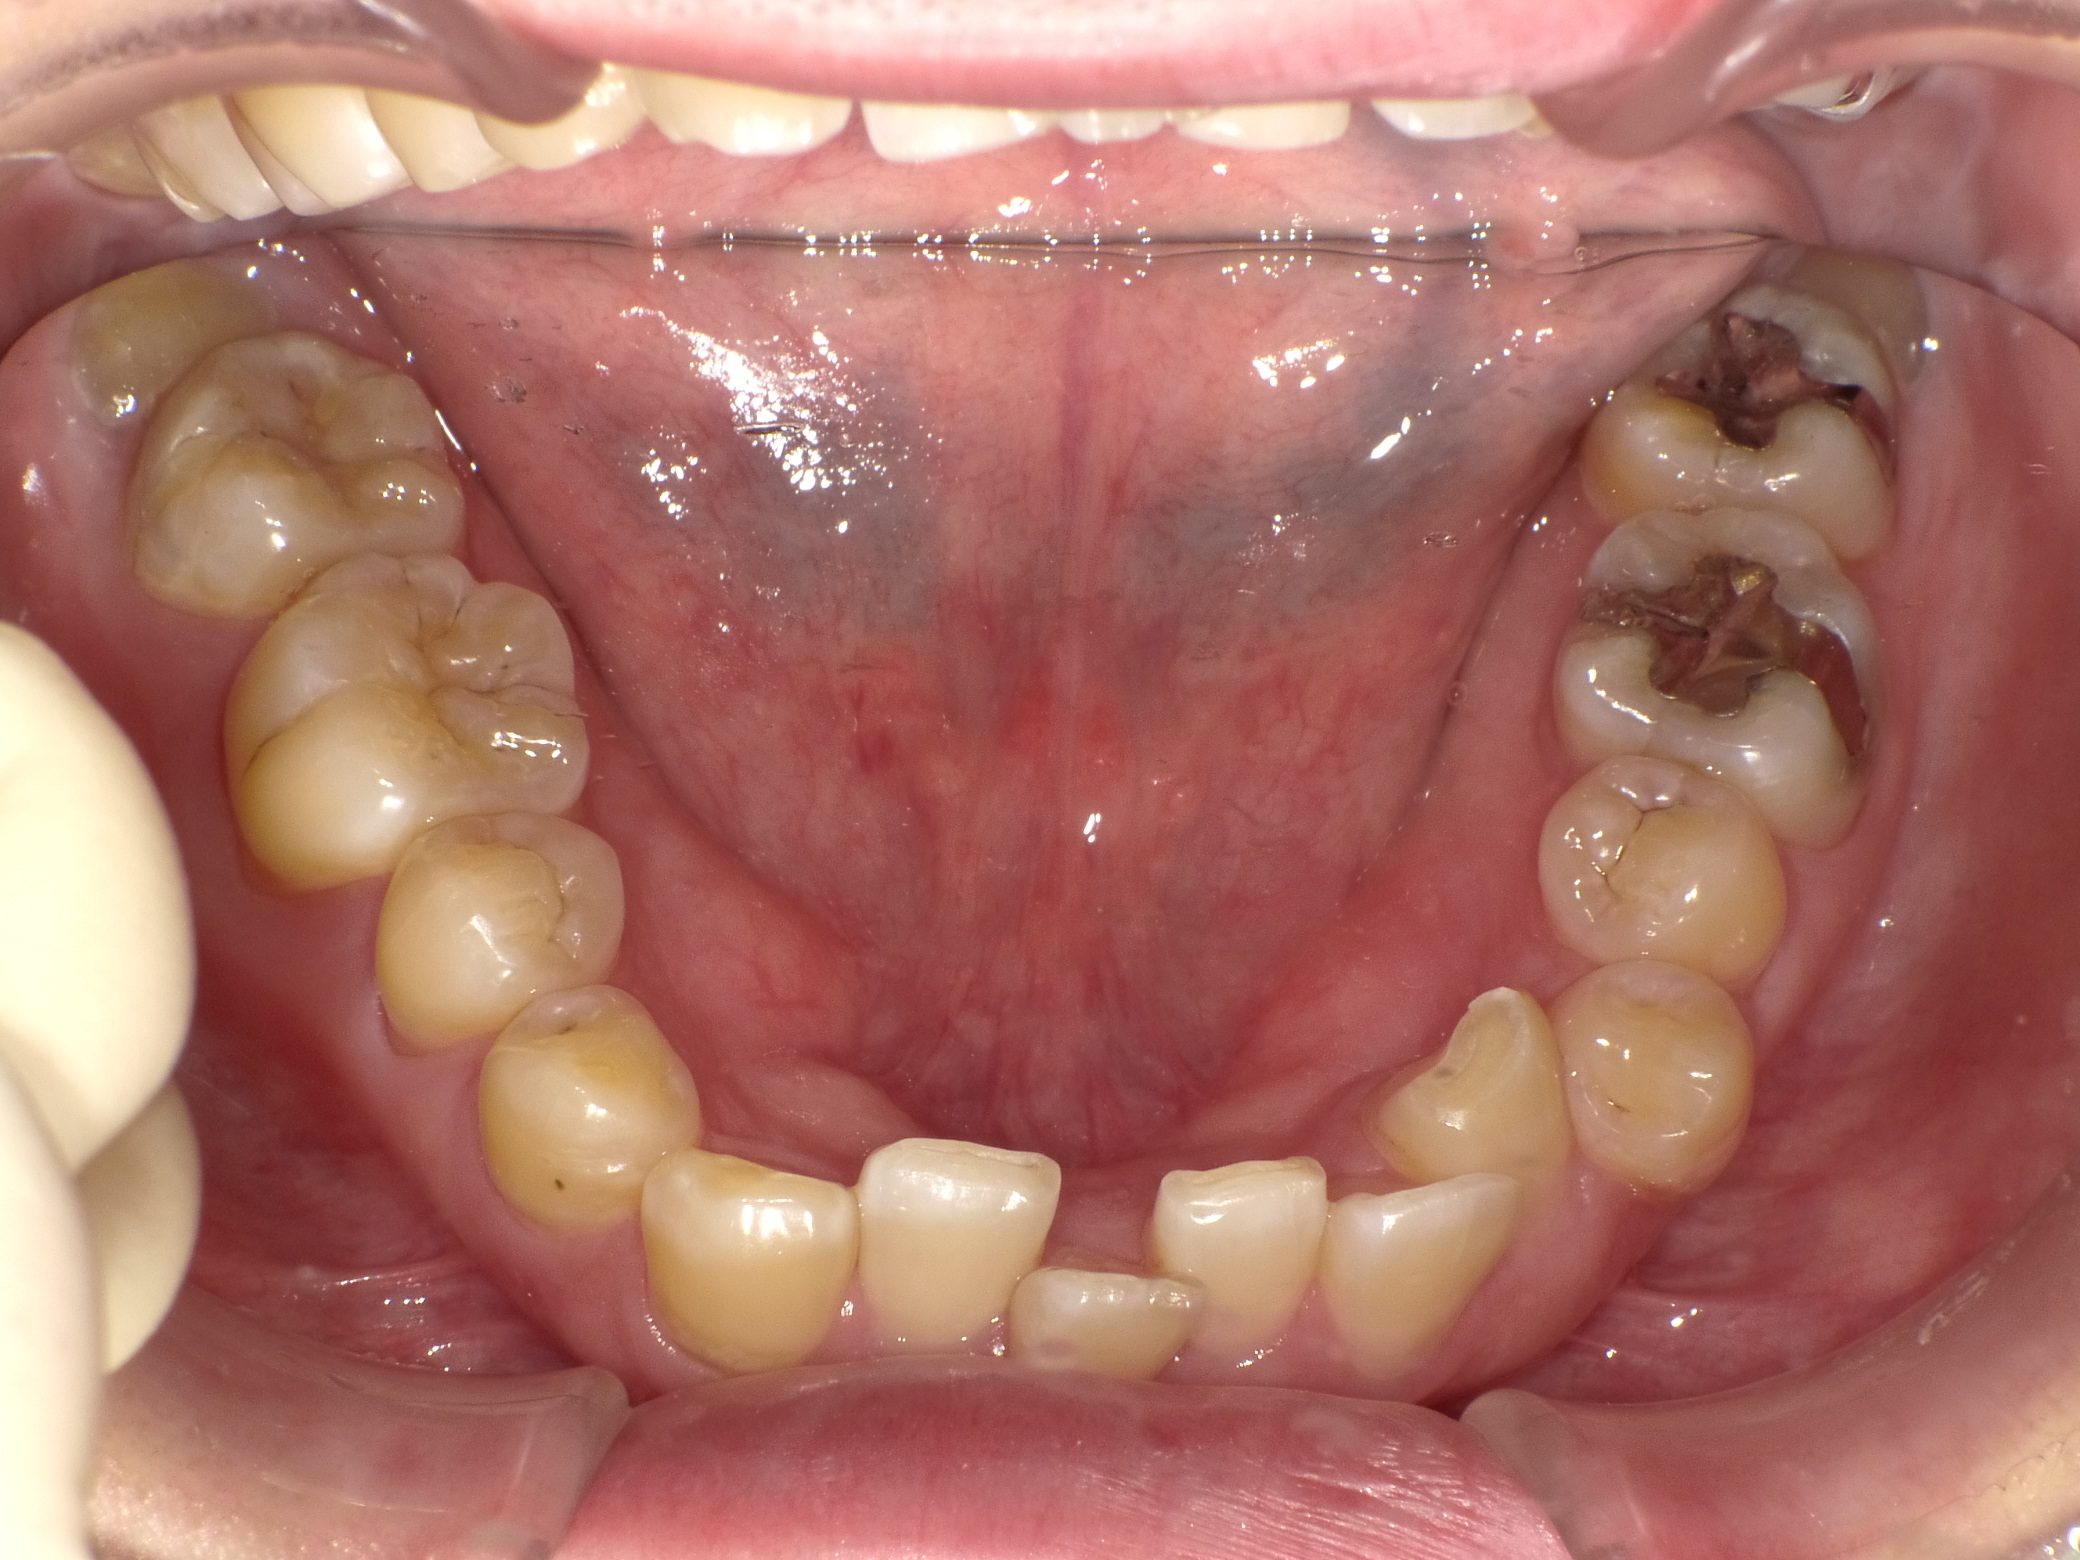

Before

After

【社会人】インビザラインフル 反対咬合(受け口)を改善 下顎前歯1本抜歯

全く装置の浮きがなくしっかり使ってくれたので2年で終了しました。

10年前の治療ですが、今もしっかり後戻りせずに歯並びを保たれています。